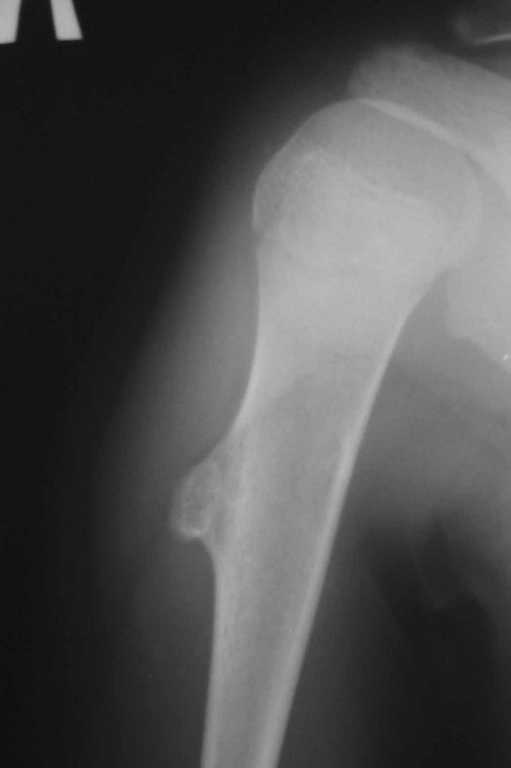

У 12-летнего мальчика образовалась припухлость на верхней трети плеча.

Рентгенобслежование выявило такую картину (см. прикрепленные файлы). Нельзя исключить

энхондрому диафиза плечевой кости. Какую тактику лечения выбрать: экскохлеация или